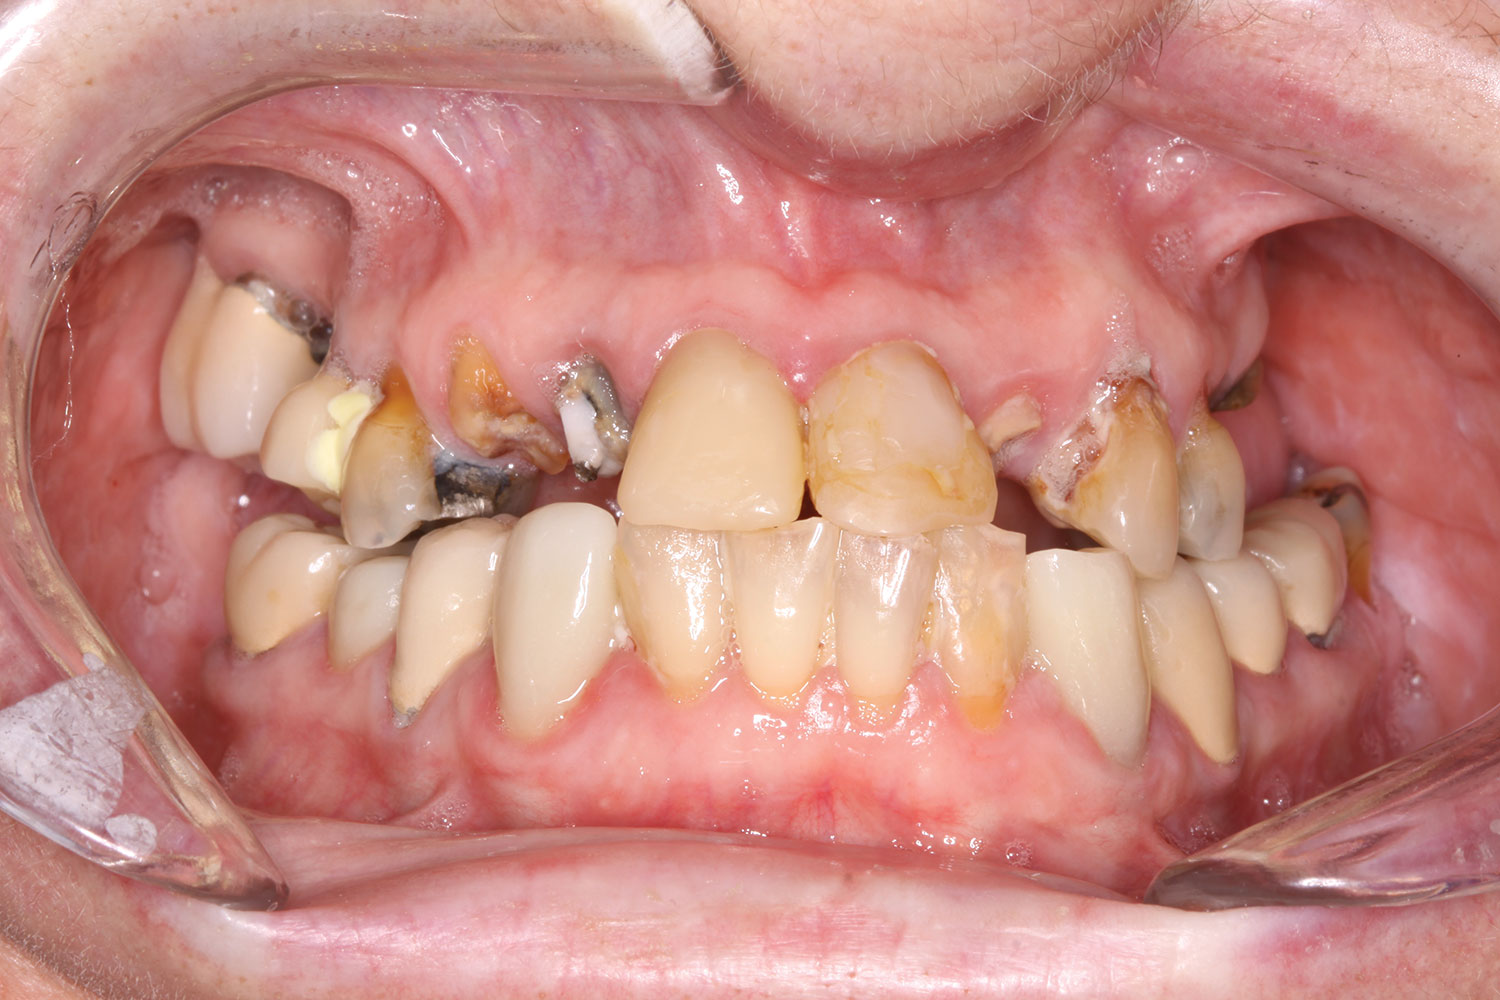

Case 3

A 67-year-old female patient presented with a highly compromised maxillary and mandibular dentition, including teeth Nos. 2 through 15, 17, 21 through 24, and 27 through 30. Soft tissues were of normal contour, and bone profiles were generally sustained and favorable. The patient was excited about the prospect of transforming both her maxillary and mandibular compromised esthetics and function in one visit. (Case 3 is depicted in Figure 23 through Figure 42.)

Fig 25. Initial clinical presentation, intraoral view.

Figure 25